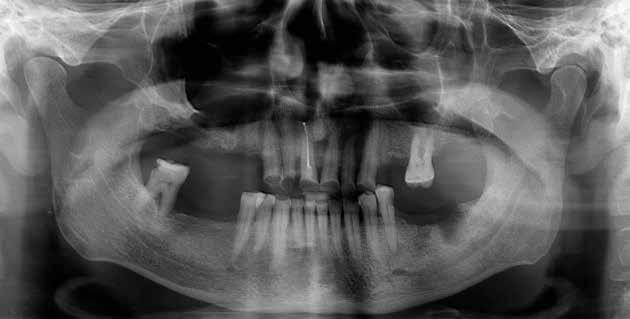

Alla visita di rivalutazione è emerso un ulteriore peggioramento della situazione, confermata anche dall’esame radiografico, con parodontopatia, sanguinamento al sondaggio, infiammazione diffusa, alitosi, difetto parodontale verticale mesiale a 2.3, residui radicolari 1.4, 1.6, 1.7, 3.6, 3.8 e carie destruenti di 1.5, 2.6, 3.5, 3.7 (con lesione endoperio) e 4.7 con estrusione e carie (Figg. 1, 2)

Prima di procedere con gli interventi si è richiesto degli ematochimici di routine, per controllare soprattutto la glicemia, l’emoglobina glicata, la coagulazione, la vitamina D e i sali minerali.

Al controllo ematologico è emersa una emoglobina glicosilata molto superiore la percentuale accettabile a procedere (il valore era 9,3%) e deficit di D-25OH che è stato risolto con una terapia di ripristino con colecalciferolo 25000 U.I. Data la stretta correlazione tra emoglobina glicata e affezioni orali, è ormai routine seguire un percorso che porta alla bonifica della bocca e contestualmente, che aiuta il paziente anche con il controllo della glicemia. In prima battuta comunque, abbiamo sottoposto il paziente a una seduta orale. Per via del suo stato di salute (abbiamo stabilito per lui un rischio alto) durante ogni seduta invasiva abbiamo sempre monitorato il paziente con rilevazioni multiple dei parametri e reperendo un accesso venoso pe-

riferico. Si è eseguito la maggior parte delle estrazioni in un’unica seduta operatoria, a esclusione degli elementi 2.6 e 4.7 che sono stati mantenuti perché presentavano mobilità ma non segni di focolai infettivi attivi e che si è deciso di estrarre in un secondo momento. Il follow-up post estrattivo ha consentito anche di valutare la risposta tissutale e la guarigione degli alveoli. Non è stata sospesa la terapia con l’acido acetilsalicilico. Il PRGF è stato importante per evitare alveoliti che avrebbero rallentato la guarigione (Figg. 4-6).

Dopo tre mesi dalla prima fase estrattiva sono stati ripetuti gli esami ematochimici dai quali l’emoglobina glicata del paziente è scesa a 7.2%. Abbiamo pertanto avviato con lo studio pre-implantare che prevede la ceratura diagnostica e gli esami radiologici più avanzati per scegliere i giusti impianti e la loro sede corretta.

L’esame CBCT ha rivelato un quantitativo di osseo sufficiente a procedere con l’intervento implantare, anche se erano ancora visibili le zone delle estrazioni; inoltre ha evidenziato una lesione osteolitica a carico del 3.5 che abbiamo dunque deciso di estrarre (Figg. 7-20).